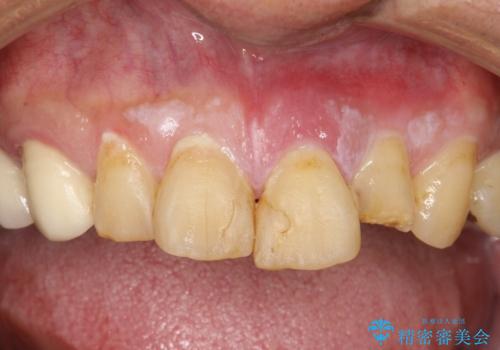

- 左の前歯で硬いものを咬んだら、歯からバキッと音がしてその衝撃で痛みが出た、その後前歯がゆれると来院されました。

左上1が水平的に割れている状態で、歯冠を取り除くと神経が露出しており、唇側はかなり歯肉縁下で破折しており、そのままではかぶせものを入れるのは難しい状態でした。

抜かずになるべくその歯を残して使っていきたいとのことで、

根管治療をした上で歯を引っ張りだして(エクストリュージョン)、その後、骨外科にて歯周組織を整えた上で、かぶせものを入れていく治療計画をたてました。